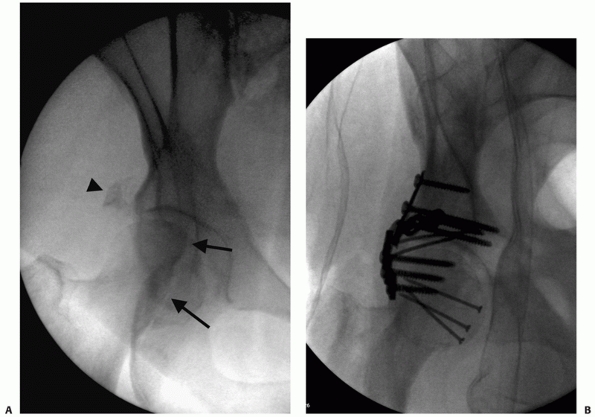

FIGURE 45-1 A.

Anteroposterior (AP) radiograph in traction of a 42-year-old man at the time of transfer to our center, 3 weeks after sustaining a displaced transverse right acetabular fracture in a motor vehicle accident. Subsequently, open reduction and internal fixation was performed. B. AP radiograph at his 20-year follow-up examination. The patient had returned to full activities within 1 year of his accident and continued to be asymptomatic regarding the right hip. (Copyright Berton R. Moed, MD.) |